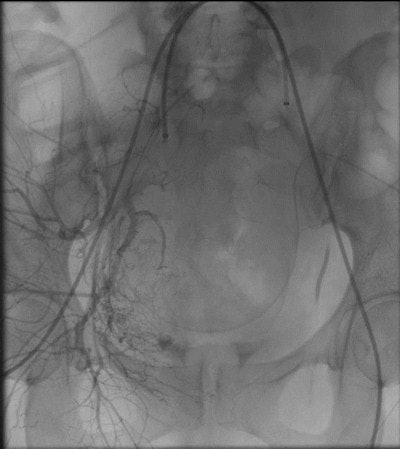

Embolization is a well-established interventional radiology technique that blocks blood vessels, controlling hemorrhage. Interventional radiologists guide a catheter up a uterine artery using x-ray imaging. Once at the site of bleeding, clotting agents, such as tiny sponge-like gel foam particles (the size of sand) or little metal coils, are released to block an injured vessel and stop the bleeding.

Over the last two years, 12 women (ages 28-46) who urgently needed uterine arteries ballooning and embolization to prevent and control bleeding after a C-section were referred to the interventional radiology service at Al Ain Hospital. Seven of these women were diagnosed with invasive placenta that was confirmed by a predelivery MRI. Interventional radiologists worked in a multidisciplinary team with obstetricians. The interventional radiologists guided balloon catheters into a woman's left and right uterine artery (preoperative prophylactic insertion of bilateral internal iliac artery occlusion balloons) before delivery -- to be ready to inflate (just like in angioplasty), if needed at delivery to block excessive blood flow.

After delivery, if an invasive placenta could not be delivered, the obstetrician left the placenta in place; interventional radiologists used uterine artery embolization -- with absorbable gelatin sponge -- to close blood vessels to the placenta, in essence, cutting off its blood supply so that it would die and eventually be reabsorbed by the body.

Our retrospective evaluation for the intraoperative blood loss was very interesting, finding that obstetricians immediately see a dramatic decrease in bleeding once the balloons are inflated, allowing for easier surgical intervention. Bleeding complications after C-sections are uncommon but can happen either immediately after the C-section or up to several weeks after the delivery. A specific type of injury to the blood vessel known as a pseudoaneurysm, which is a contained blood vessel rupture, tends to show up later. Overall, regardless of any of the clinical circumstances, bleeding following C-section was stopped promptly and effectively with minimal complications by embolization procedures performed by interventional radiology.